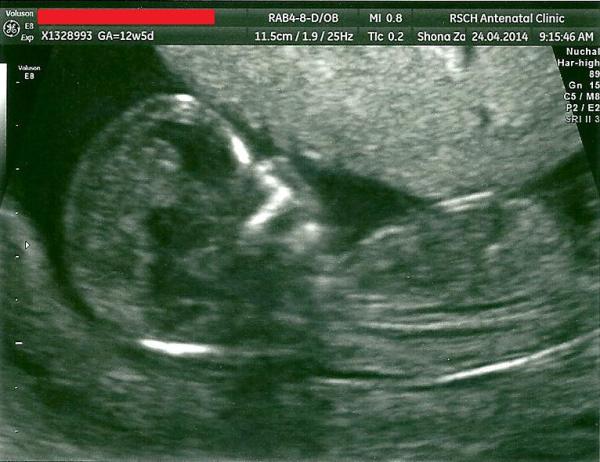

Thanks Mumsnet for deleting that last one! Forgot my full name and d.o.b was on the scan. Here we go with that removed!!! My new little minion! Grin